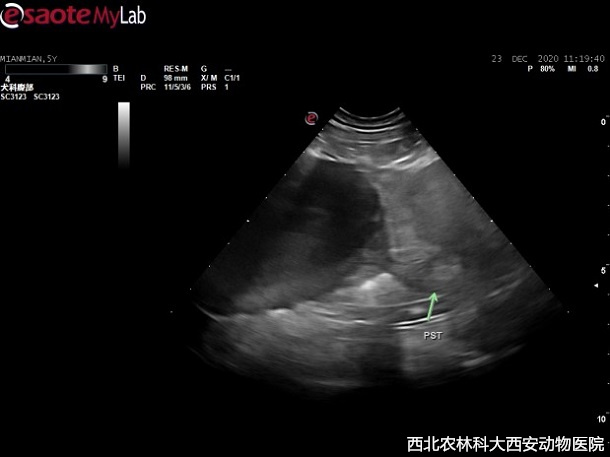

輔助檢查:主人自帶腹部平片顯示前列腺增大,膀胱前列腺區(qū)域有一明顯占位待查。超聲提示:前列腺增生且伴有囊腫,緊鄰前列腺和膀胱可見無回聲異常囊性占位,與周圍組織有聯(lián)系,疑似粘連見(圖1)。

圖一